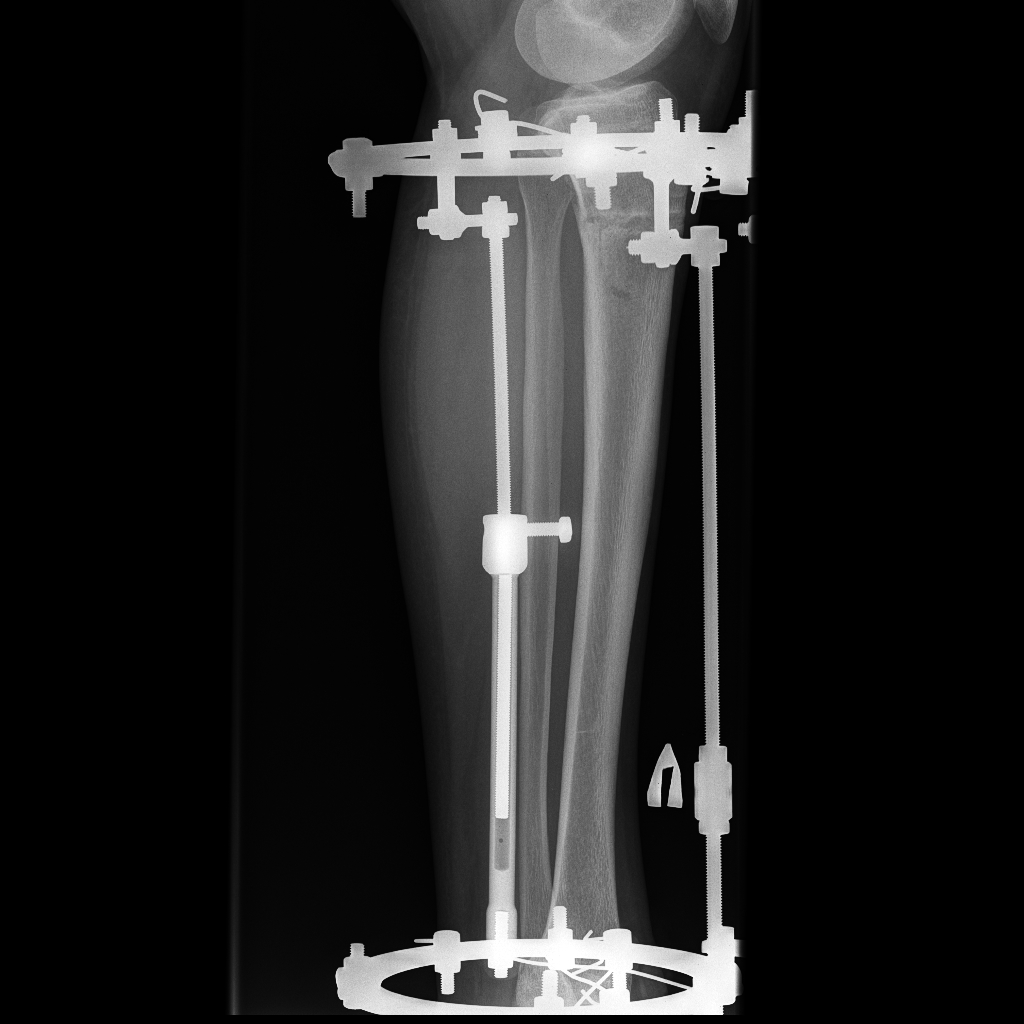

60 дней с момента операции.

Можно снимать аппараты

, но мы подстрахуемся ещё на 2 недели

!